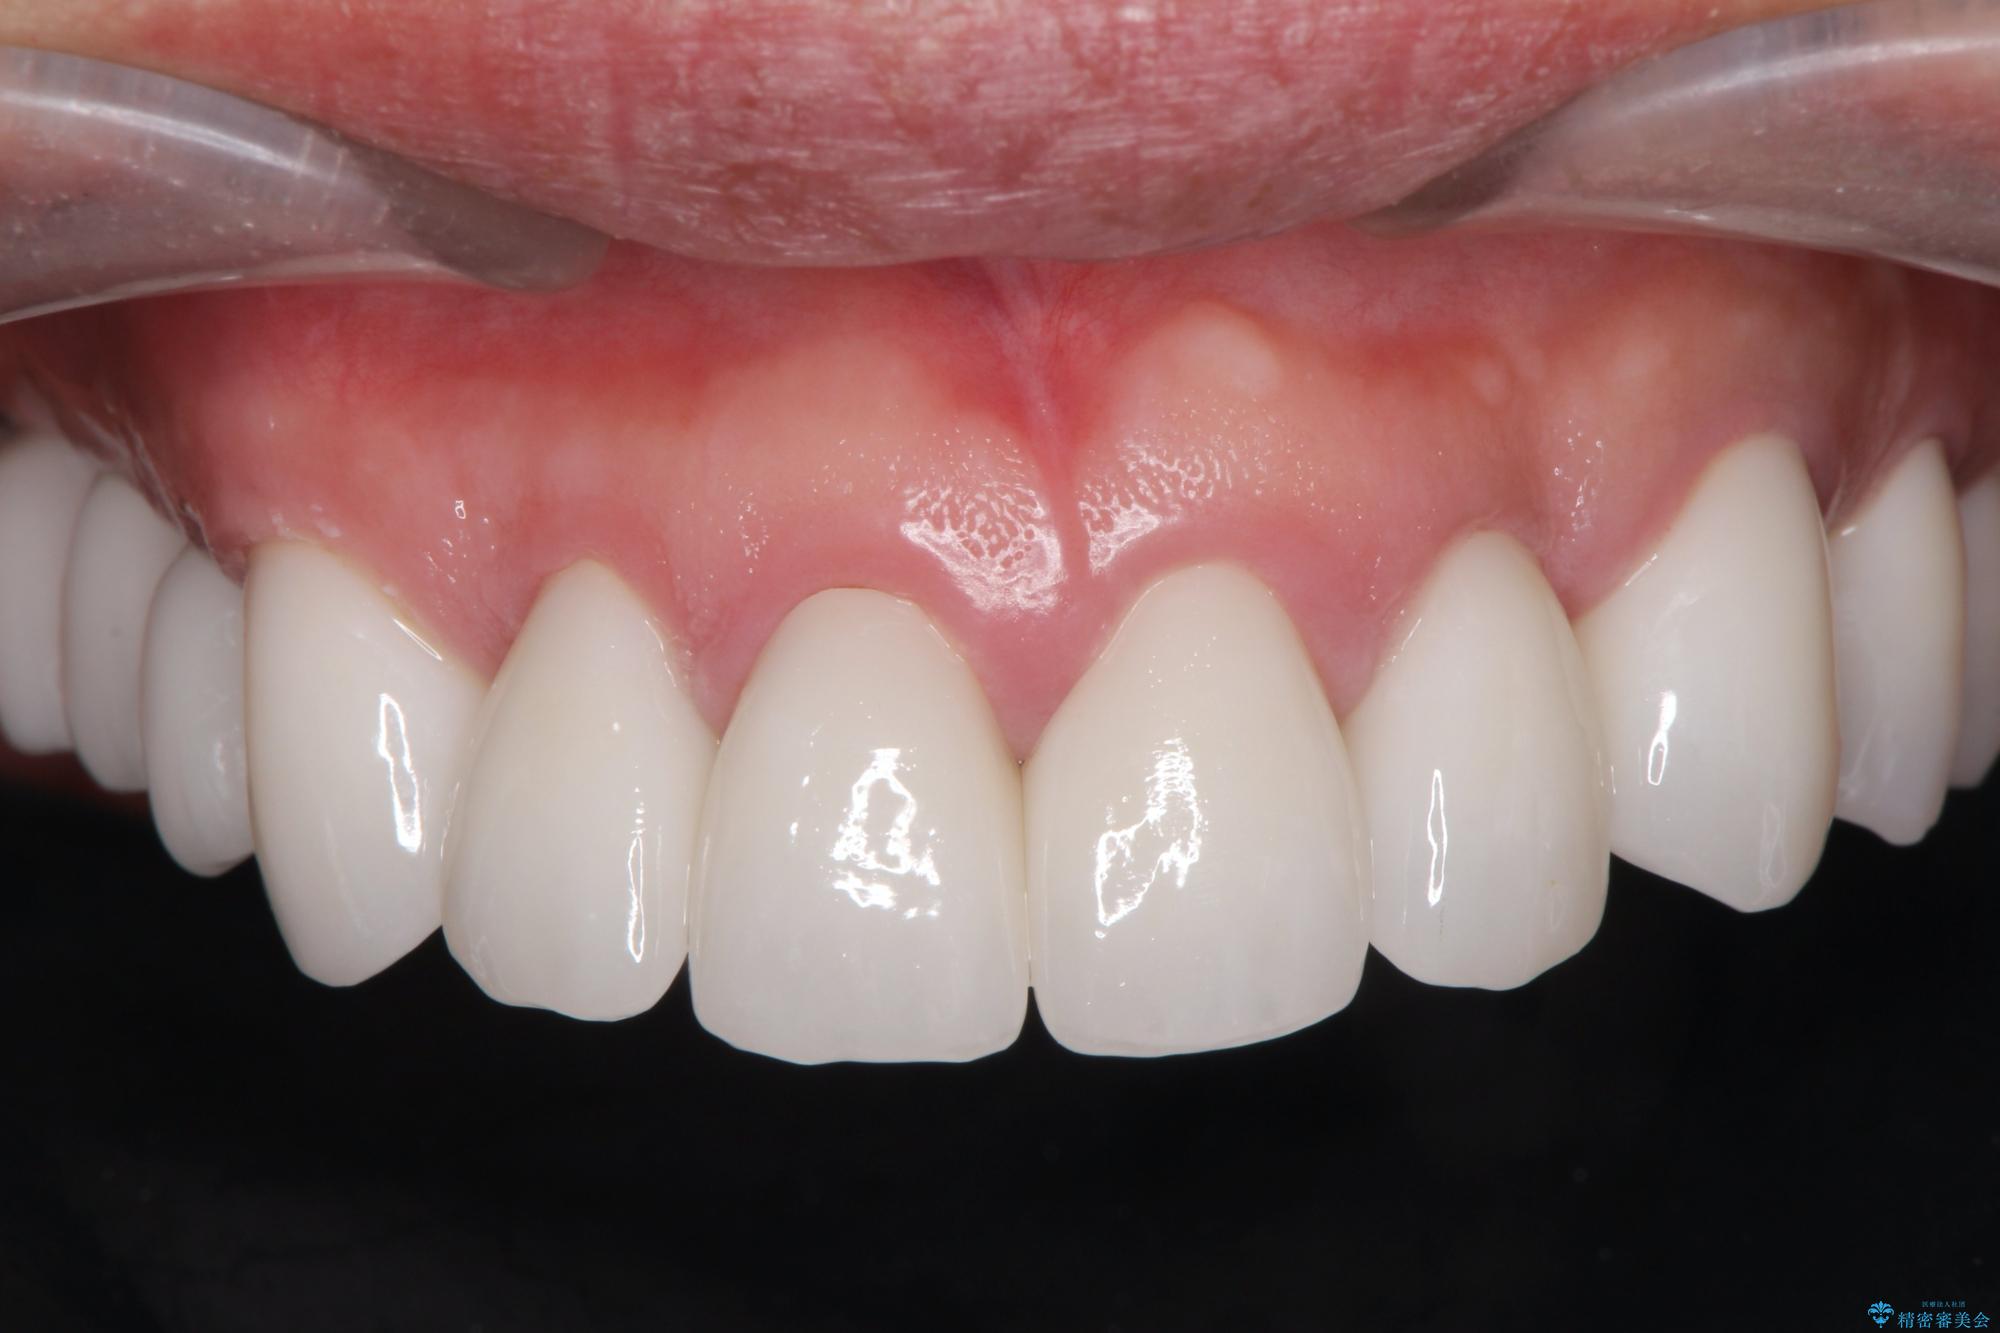

セラミッククラウンを除去し仮歯を装着し、歯周外科手術を行い歯ぐきの状態を改善したのち、適合の良いセラミッククラウンを再作製をする治療計画としました。

- 90.2万円(ジルコニアクラウン×6・仮歯×6 ・歯周外科手術)費用は治療当時の料金となります

見た目の良いクラウンが装着されていても、歯ぐきの状態が悪ければ違和感や歯ぐきの腫れ、臭いの元となっていることが多く見られます。